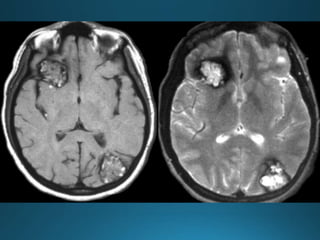

Giant cerebral aneurysms are ones that measure >25 mm in

greatest dimension.

Most commonly represent saccular cerebral aneurysms but

may also be fusiform or serpentine in morphology .They are

thought to develop via two pathways :

• internal elastic lamina de novo defect

• enlargement from a smaller aneurysm

MRI

On MRI also the patent and thrombosed aneurysm display different imaging

features:

T1

most of the patent aneurysm appears as flow void, or they may show

heterogeneous signal intensity

in thrombosed aneurysm appearance depends on the age of clot within the

lumen

T2

typically hypointense

laminated thrombus may show a hyperintense rim